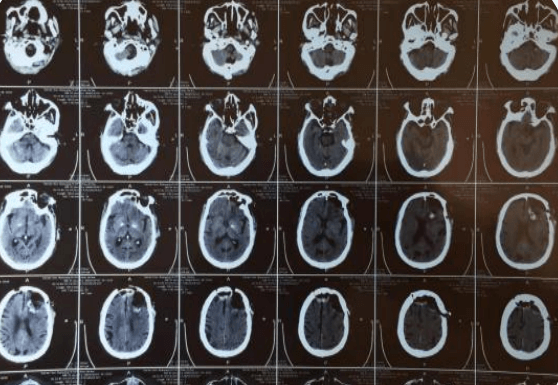

約3個月前,趙大爺在我院查顱腦CT示:左側額顳部占位,多考慮腦膜瘤;右側額部皮下脂肪瘤,當時患者無明顯癥狀,選擇保守治療,約一周前,患者出現(xiàn)意識混亂,頭悶表現(xiàn),家屬為求進一步治療,解決患者不適,提高患者生活質量,入院治療。在劉小雷主任和游文良副主任醫(yī)師的指導下,經(jīng)過醫(yī)護一體化協(xié)作模式的共同努力,為78歲高齡的趙大爺術前制定精準的手術方案,術中在病人家屬的許可下,實施顯微鏡下顱內腫瘤切除術,經(jīng)過精細的手術操作,手術順利完成,并且一并切除右側頭皮脂肪瘤,顱內外問題一起解決,護理團隊根據(jù)患者病情特點制定了護理計劃及護理措施,密切觀察患者瞳孔意識變化,肢體活動情況,觀察患者生命體征變化,二十四小時出入量是否平衡,并詳細的記錄各項指標的變化,在護士專業(yè)而細致地看護下,術后五天,患者無任何不良反應,恢復良好,身體各項指標一切正常,無后遺癥。在神經(jīng)外科二病區(qū)醫(yī)護團隊的精心治療和護理下,趙大爺病情日見好轉,家屬臉上也露出了久違的笑容。